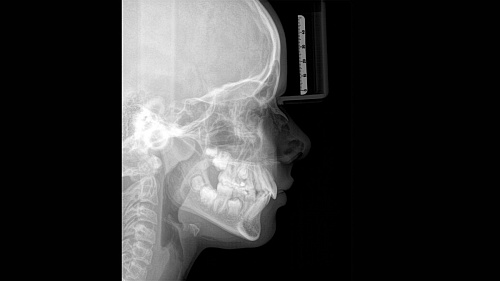

При помощи такого оборудования специалист сможет успешно решить широкий спектр диагностических и лечебных задач. Качественное изображение, достоверность при разноуровневой резкости (технология Sharp Layer), гибкий объём, 30 доступных вариантов цвета. Цефалометрическая визуализация позволяет получать боковые или симметричные снимки, а также определить положение при смещении зуба. Работая при разрешении до 80 мкм в режиме низкой дозы и HD, вы получаете качественные изображения выбранного формата, заботясь о комфорте и безопасности пациента.

ORTHOPHOS SL 2D использует цветовые сигналы и специальные символы для изображения правильной схемы положения головы пациента, причём данный процесс происходит автоматически. Фиксация происходит в трёх точках, опорой человеку служат поручни. Высокое качество снимка помимо прочего, обеспечивается за счёт автоматического измерения расстояния между височными областями головы. Съёмочный блок двигается по индивидуальной для обследуемого траектории.